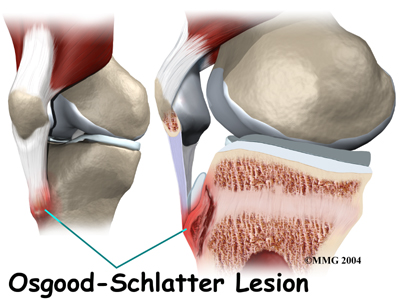

Overuse syndromes are common in active adolescents. Stress fractures of the foot, patellofemoral joint problems, and are examples of overuse syndromes.

Stress fractures and Osgood-Schlatter’s usually respond well to a discontinuation of the activity that caused them while continuing exercises like swimming and stationary biking to maintain conditioning. Your Chiropractor can provide advice on how to best maintain fitness and can design an individualized program for your child to follow while their injury heals.